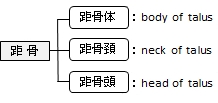

距骨は以下の4つの骨と接して3種類の関節を形成する。

1 |

距骨(距骨滑車:距骨滑車上面、内果面)⇔ 脛骨(下関節面、内果関節面) | ||

2 |

距骨(距骨滑車:外果面)⇔ 腓骨(外果関節面) | ||

3 |

距骨(後踵骨関節面)⇔ 踵骨(後距骨関節面) | ||

4 |

![]()